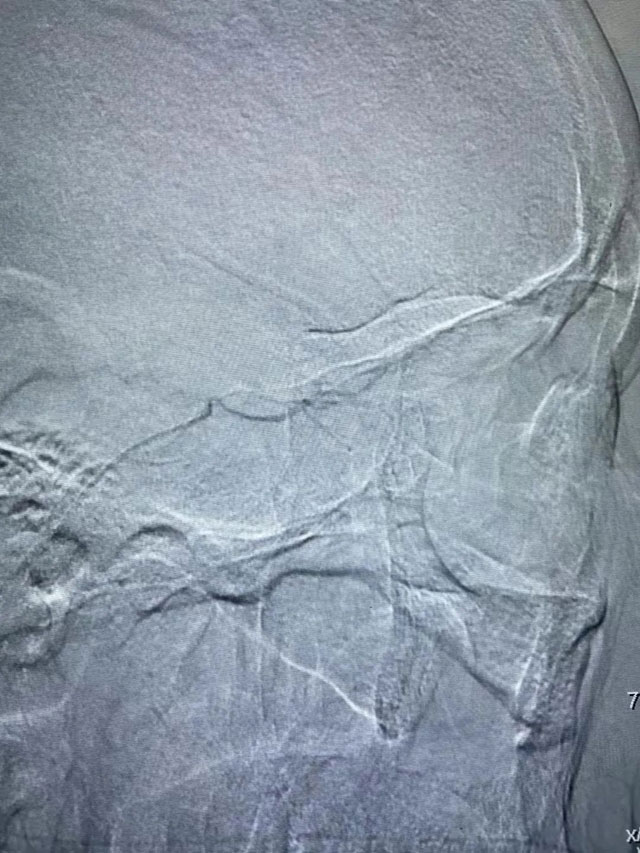

前些时候贾老先生右眼突发失明5小时,在家属陪同下,前来东方总院急诊科,1月24日晚上接到急诊会诊后,被诊断为:眼动脉栓塞导致眼动脉急性缺血引发的突发性失明,俗称“眼卒中”。黄旭东院长得知贾先生已经失明5小时了,而经皮眼动脉溶栓治疗最佳手术时间是失明后6小时以内,情况十分紧急!时间越久,失明风险越大,看着贾先生家属焦急的脸,黄院长当机立断,立即紧急启动眼动脉溶栓治疗绿色通道,为贾先生量身定制了手术方案。当天晚上,黄旭东介入团队放弃了晚上休息时间,在导管室老师们的配合帮助下,进行术前介入溶栓准备,为贾先生进行了手术。

目前,国内针对“眼卒中”主要是采取动脉顺行眼动脉介入溶栓治疗,最佳治疗时间是6小时以内,且顺行眼动脉介入溶栓经脑血管,路径长、风险大,容易造成脑出血、脑梗等问题。而贾先生的手术历时仅1个小时,就顺利完成。术后,贾先生睁开眼睛第一句话就是:“我又能看见啦!淮南东方医院介入科的专家就是厉害!”目前,贾先生视力已恢复到眼前50cm指数。